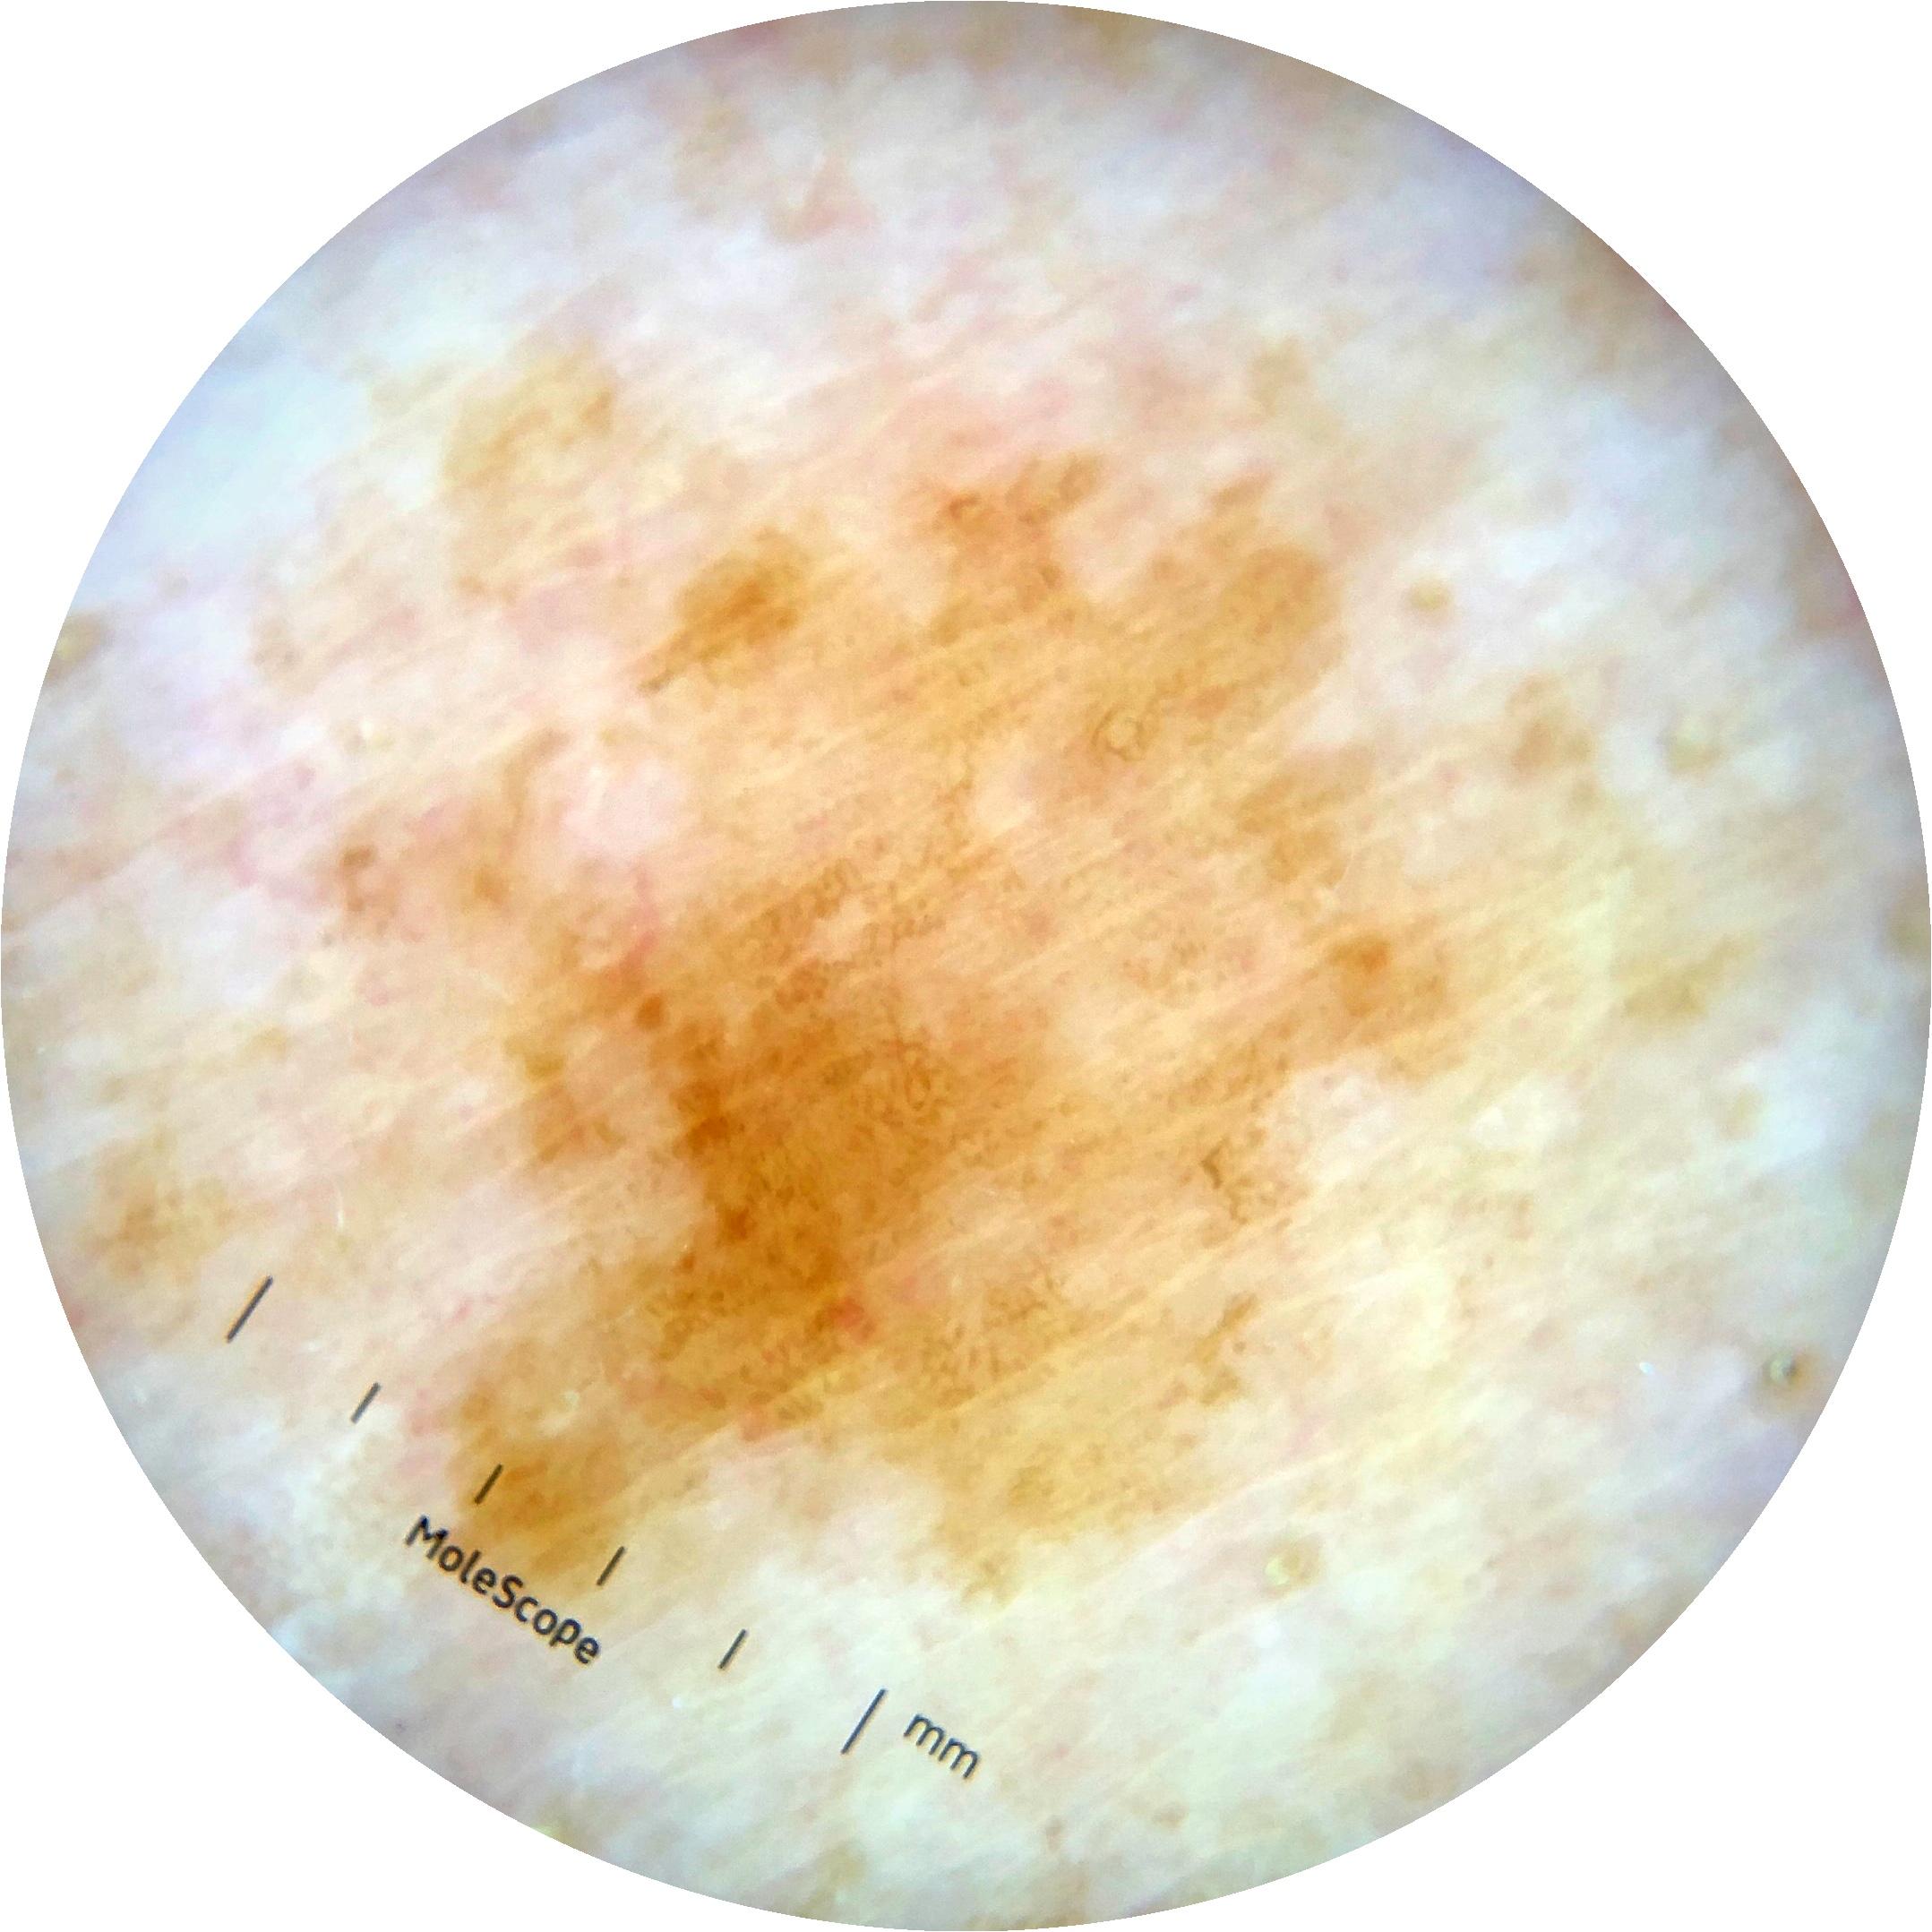

ISIC_5016821

2181 x 2181

Clinical

Field Value

acquisition_day 122

age_approx 75

anatom_site_1 Trunk

anatom_site_2 Posterior trunk

anatom_site_general posterior torso

concomitant_biopsy False

diagnosis_1 Benign

diagnosis_confirm_type single image expert consensus

family_hx_mm True

image_manipulation instrument only

image_type dermoscopic

lesion_id IL_1445651

patient_id IP_6868575

personal_hx_mm True

sex male